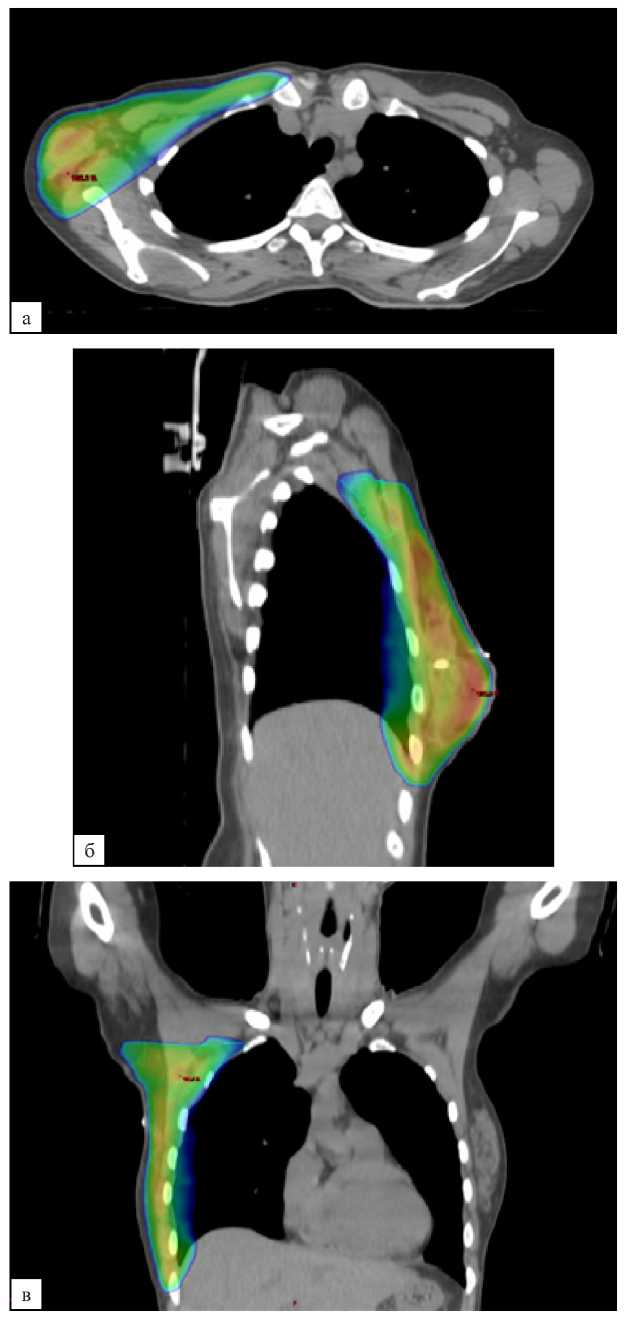

В контрольной группе послеоперационная лучевая терапия проводилась в стандартном объеме — облучение оставшихся тканей молочной железы (после органосохраняющего лечения) или мягких тканей передней грудной стенки (после мастэктомии) с подмышечными ЛУ I, II, III уровней и надключичными ЛУ (рис. 2, а, б, в). При планировании объемов облучения в исследуемой группе из объема облучения исключались подмышечные ЛУ III уровня и надключичные ЛУ (рис. 3, а, б, в). Оконтуривание всех указанных структур выполнялось согласно рекомендациям ESTRO от 2015 года [15].

Рис. 2 (а, б, в). Дозиметрический план лучевой терапии молочной железы, надключичных и подмышечных лимфатических узлов I, II, III уровней. а — аксиальная проекция; б — сагиттальная проекция; в — фронтальная проекция

Fig. 2 (а, б, в). Dosimetric plan of breast RT, supraclavicular and axillary lymph nodes of levels I, II, III. a — axial plane; б — sagittal plane; в — frontal plane